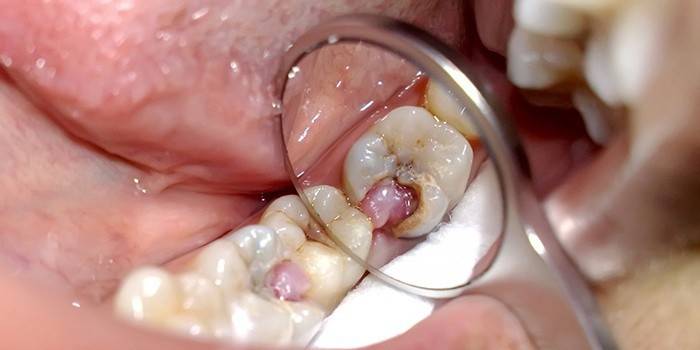

- Pulpito. Cárie não tratada no tempo atinge a polpa e causa sua inflamação. Há dores graves que exigem um tratamento radical: remoção de nervos abertos e preenchimento de canais.

Clínicas modernas realizam a despulpação de maneira mais suave e segura. O problema é resolvido em uma visita ao dentista, graças à introdução da anestesia. Usando ferramentas especiais, o médico fornece acesso à polpa e remove completamente o tecido afetado. Isso leva aproximadamente 30 minutos, levando-se em consideração a limpeza completa dos canais e a instalação de um selo (temporário, se o dentista quiser ter certeza de uma despulpação completa ou permanente).